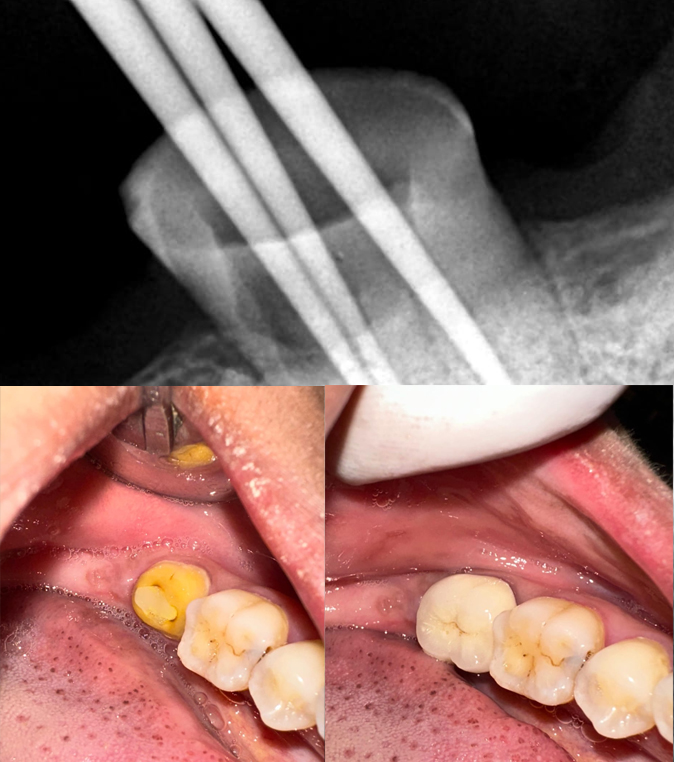

Root canal treatment

Root canal treatment is a safe and effective way to relieve severe tooth pain and save your natural tooth. At our clinic, we use advanced technology and gentle techniques to ensure a comfortable, stress-free experience. The procedure removes infected or damaged tissue from inside the tooth, eliminating pain and preventing further issues. Our skilled dental team focuses on precision, cleanliness, and patient comfort every step of the way. Root canals are often completed in just one or two visits with minimal recovery time. We ensure your treated tooth is restored with a strong, natural-looking crown for lasting protection. Don’t let tooth pain affect your daily life—get the care you need today. We offer flexible appointments and personalized care to suit your schedule. Experience relief, restore your smile, and protect your oral health. Book your consultation now and take the first step toward a pain-free smile!